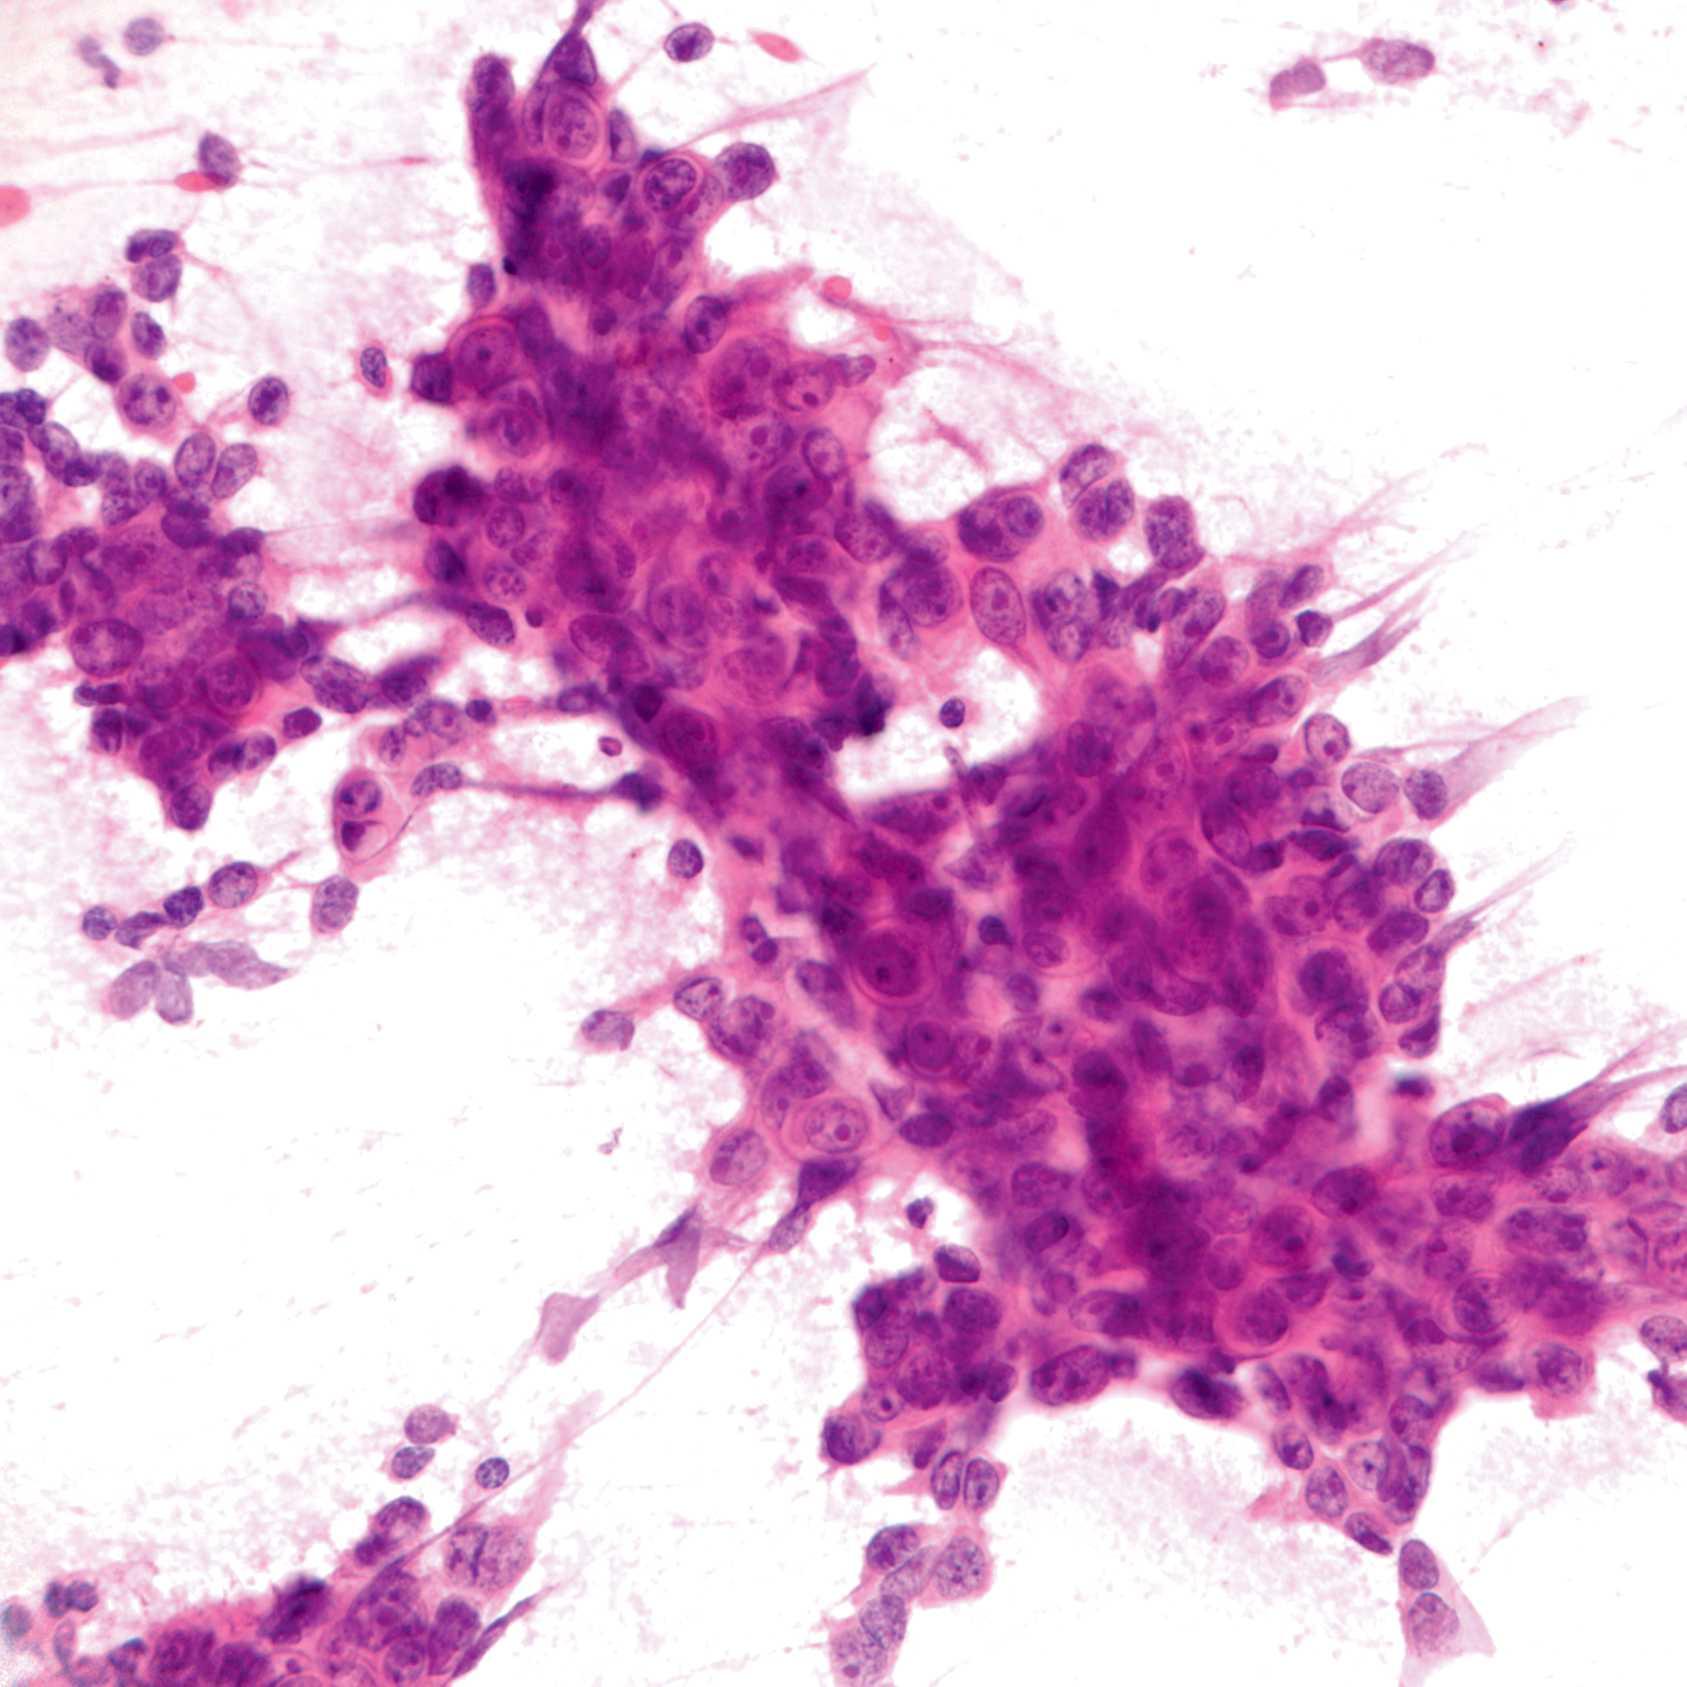

IntraoperativeConsultation:Gross Findings

IntraoperativeConsultation:Microscopic Findings